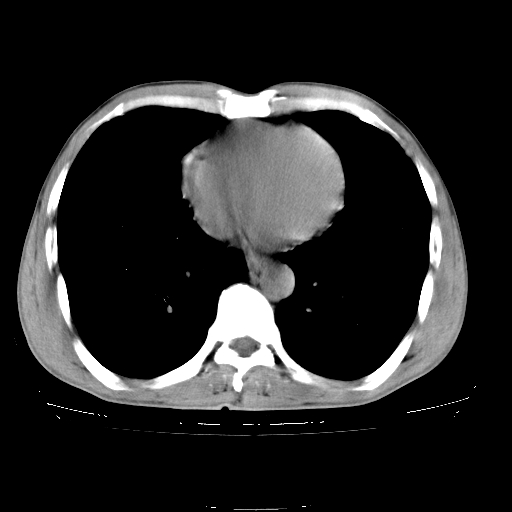

以下是引用yangyudong333在2008-4-29 5:38:00的发言:[br]比较典型的矽肺结节.支持[br]诊断依据:[br] 1.x线表现:[br] ①典型矽肺为多发直径 1~3mm 小结节,即矽结节,由胶原纤维和硅尘构成,可融合成团块,好发于上肺。[br] ②团块周围常有肺大泡。[br] ③胸内淋巴结增大、钙化。如肺门淋巴结呈蛋壳样钙化有助于与其他尘肺区别。[br] ④胸膜常广泛粘连、增厚。[br] 2.ct表现[br] ①两肺散在大小较为一致的小结节影,其密度较高,边界清楚。[br] ②小结节可融合为较大团块影,直径约 1cm ,甚至可达 10cm以上,易发生在上叶。[br] ③小结节周围常并有小叶中心气肿或弥漫性肺气肿。

以下是引用liuyue在2008-4-28 22:30:00的发言:[br]比较典型的矽肺结节.[br]请结合临床及化验除外矽肺合并肺结核之可能.